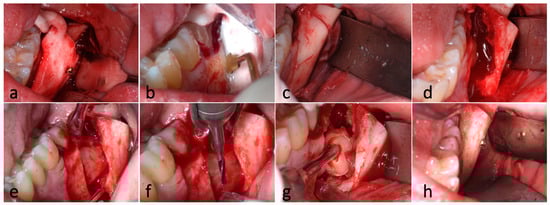

2. Description of the Cases